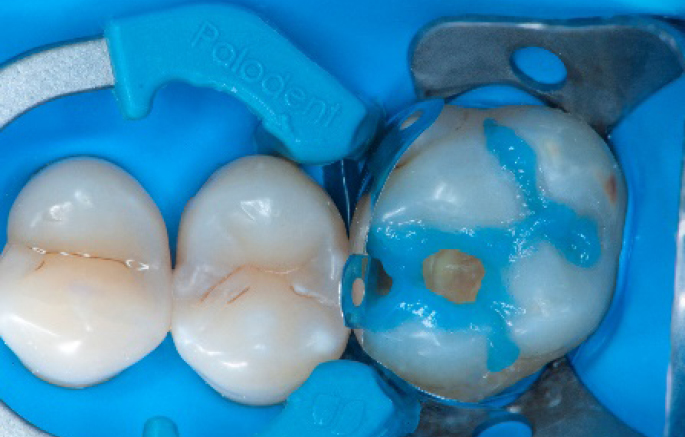

The complete Palodent1 system in place: sectional matrix, wedge and ring.

Step 5:

Buccal view of the Palodent1 system.

Selective enamel etching procedure with Conditioner2.

Transformation of class II into class I, restoring the interproximal wall with Spectra ST4 composite in shade A2.